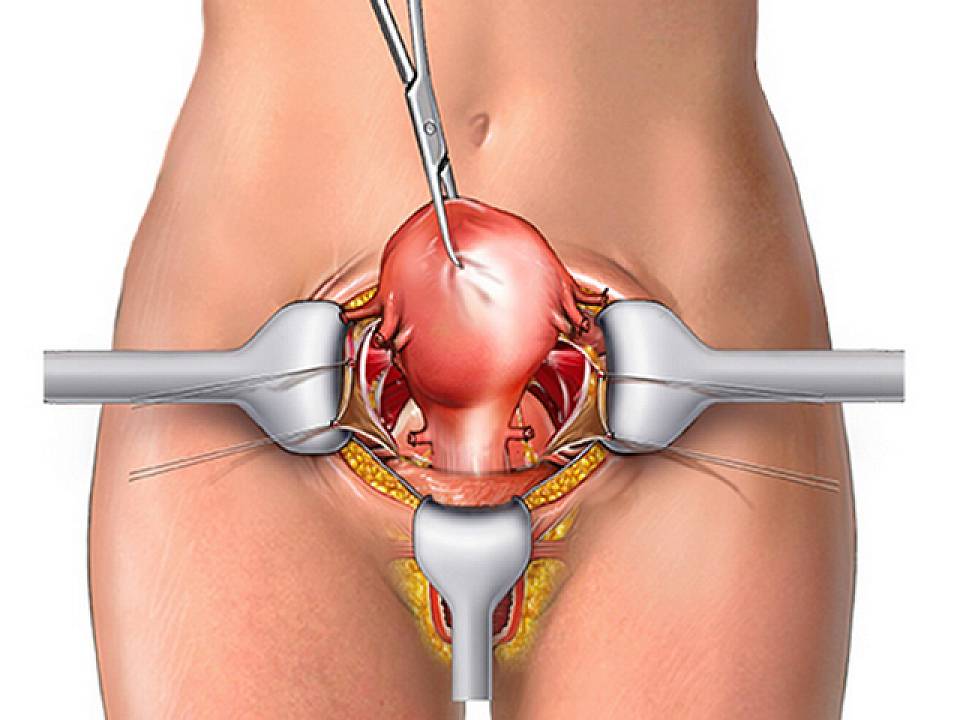

Пластика влагалища помогает не только вернуть прежнее качество сексуальной жизни, но и бороться с такой проблемой, как выпадение матки из стенок влагалища. От всех этих проблем можно избавиться буквально за считанные часы, которые пациентка проводит на операционном столе под наркозом. Через пару дней можно возвращаться к обычной жизни, не забывая выполнять несложные требования врача, чтобы пластика влагалища не стала причиной дискомфорта.

Операции при опущении и выпадении матки

Преимущества операции:

- За счет прочности тончайшей сетки обеспечивается надёжный эффект фиксации с низким риском рецидивов.

- Синтетический сетчатый материал обладает хорошей биосовместимостью с тканями человека, что предотвращает развитие аллергических проявлений, реакции отторжения, рубцовых изменений в тканях, а также воспалительных и гнойных осложнений.

- Операция проводится только лапароскопически, без разрезов в области влагалища.

- Короткий восстановительный период и хорошие отдалённые результаты.

- После проведения операции можно вести полноценную активную жизнь, в том числе — заниматься спортом.

Вагинальное удаление матки. Выполняется чаще при полном выпадении матки, может сочетаться с пластикой влагалища.

Органосохраняющие операции. Опущение внутренних половых органов не является показанием для удаления матки. Мы проводим операции с применением современных синтетических имплантатов (производства США, Франции) для коррекции всех дефектов тазового дна с долгосрочными положительными результатами. При сочетанных формах опущения (стрессовое недержание мочи) проводим операции TOT-O (установка среднеуретрального слинга трансобтураторным доступом), избавляющие от этого симптома.

Особенности операций при опущении и выпадении матки

Анестезия. Хирургическое вмешательство проводится под внутривенным, спинальным или эндотрахеальным наркозом. Вид обезболивания определяет на предварительной консультации опытный анестезиолог-реаниматолог с учётом противопоказаний и имеющейся соматической патологии.

Длительность операции. В зависимости от сложности хирургического вмешательства операция может продолжаться от 1,5 до 3 часов. В каждой конкретной ситуации операция длится столько, сколько необходимо для получения качественного результата при максимально бережном отношении к здоровым тканям.

Нахождение в стационаре. Женщина находится в нашем госпитале от 1 (без ночёвки) до 2–3 суток в зависимости от сложности операции и общего состояния. Затем в амбулаторных условиях пациентка находится на больничном листе от 10 дней до 3–4 недель.

После операции. Время восстановления организма зависит от объёма хирургического вмешательства, возраста пациентки и общего состояния её здоровья. В среднем оно составляет 2–3 недели.

Ограничения. В течение месяца после операции не рекомендуется подъём тяжестей, ограничивается половая жизнь, посещение сауны/бани. Точную длительность этих ограничений вам скажет врач при выписке.